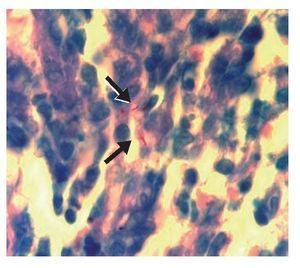

Figura 5. Tinción de Ziehl-Neelsen de biopsia de mucosa gástrica en la que se demuestra la presencia de bacilos resistentes al ácido y al alcohol (fl echas).

Mujer de 78 años de edad que ingresó al hospital por dolor abdominal progresivo. Su padecimiento se inició 6 meses antes de su ingreso con dolor abdominal urente en epigastrio, de moderada intensidad, sin irradiación, intermitente, acompañado de saciedad temprana, plenitud posprandial, vómitos, distensión abdominal progresiva y pérdida de peso de 15 kg. Su único antecedente de importancia era un Combe positivo, pues su esposo padeció tuberculosis ganglionar 10 años antes y fue tratado con agentes antituberculosos de manera satisfactoria. A la exploración física se encontró caquéctica, con signos vitales normales, cabeza y cuello sin adenopatías, ruidos respiratorios normales sin síndrome pleuropulmonar, ruidos cardiacos normales, abdomen protuberante y globoso a expensas de líquido de ascitis, con dolor a la palpación profunda, pero sin signos de irritación peritoneal, ni hepatomegalia o esplenomegalia. En los exámenes de laboratorio la paciente presentaba anemia microcítica hipocrómica, linfopenia, hiponatremia e hipoalbuminemia. La radiografía de tórax fue normal (Figura 1). La citología del líquido de ascitis informó alteraciones inflamatorias inespecíficas y no se realizó el análisis citoquímico. La tomografía computarizada de abdomen confirmó la presencia de líquido libre abdominal y además detectó un marcado engrosamiento de la pared del estómago y del peritoneo compatible con carcinomatosis peritoneal por probable neoplasia primaria en estómago (Figura 2). Se practicó una endoscopia superior, con la que se encontró una mucosa gástrica ulcerada y friable con múltiples lesiones polipoideas que afectaban el cuerpo, antro y píloro gástricos de manera circunferencial, sin condicionar obstrucción al vaciamiento gástrico; entre las úlceras se constataron áreas de mucosa respetada y una distensibilidad gástrica disminuida (Figura 3). La biopsia de la mucosa gástrica demostró infiltrado inflamatorio granulomatoso con necrosis caseosa y células gigantes multinucleadas (Figura 4). Se practicó una tinción de Ziehl-Neelsen que resultó positiva para bacilos resistentes al ácido y al alcohol (Figura 5). Una vez obtenido el diagnóstico de tuberculosis, se inició tratamiento antifímico con base en isoniacida, rifampicina, piracinamida y etambutol por dos meses, seguido de un esquema de isoniacida y rifampicina por nueve meses adicionales, con resolución lenta y progresiva de los síntomas. La vigilancia endoscópica a los seis y nueve meses documentó una mejoría franca de las lesiones de la mucosa gástrica, y en ambas ocasiones se realizaron cultivos para Mycobacterium tuberculosis de las muestras gástricas para biopsia que dieron resultado negativo. En estos momentos la paciente se encuentra asintomática y en vigilancia clínica.